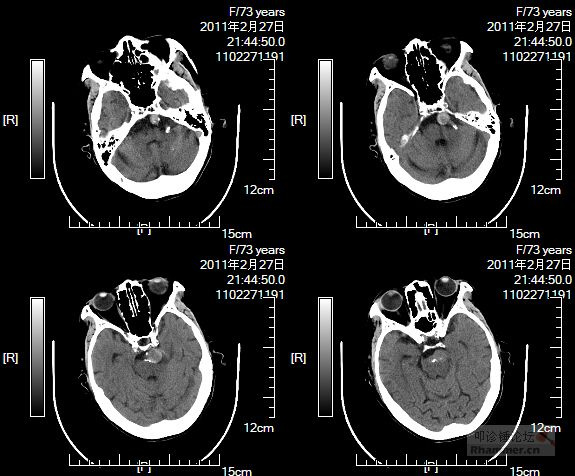

该中心收集了2008~2013年66例患者(其中33例BTAs,33例其他动脉瘤)的CT血管造影(CTA)影像,利用3D-Slicer软件进行了动脉瘤三维模型及周边血管几何形态学参数(包括血管的直径,血管与血管间的夹角等)的测量。在修正了其他形态学参数及临床变量的基础上,多元回归分析显示两侧大脑后动脉间的夹角增大(OR=1.04;P=1.42×10-3)以及基底动脉的直径变小(OR=0.23;P=0.02)都与BTAs的形成密切相关。

临床资料统计表明,基底动脉瘤组与非基底动脉瘤组间影响动脉瘤发生发展的风险因素包括患者的年龄、性别、高血压病史以及吸烟史均差异无统计学意义,而患者的家族史在BTA组中显著高于非BTA组,这两组间差异有统计学意义(P=0.01)(表1)。两组基底动脉的直径、大脑后动脉P1段的直径差异无统计学意义,而大脑后动脉P1-P1角差异有统计学意义(P=1.31×10-5)。

单变量分析表明,基底动脉瘤的形成与更小的基底动脉直径以及大脑后动脉P1段直径间更大的差异有相关,但这些相关性差异无统计学意义。多变量分析表明,更小的基底动脉直径与更大的P1-P1角与基底动脉瘤形成密切相关(表3)。

颅内动脉瘤形成的原因有遗传、不良生活习惯以及血管解剖形态、构造等综合性因素共同构成。而其中血管壁组织结构,血管解剖形态形成的血流动力学改变在动脉瘤的形成中扮演着重要角色。本篇作者通过在CTA影像上测量基底动脉直径以及双侧大脑后动脉之间夹角发现更小的基底动脉直径及更大的双侧大脑后动脉之间夹角与形成基底动脉顶端动脉瘤形成密切相关。从而认为这是一种简单、快捷排查基底动脉瘤高危患者及风险评估的方法。